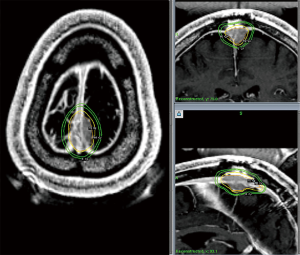

Otherwise, SRS for recurrent GBM is supported by a series of small prospective and retrospective series with either hypofractionated stereotactic radiotherapy or SRS, often with concurrent bevacizumab, with an expected 10–14 months MS following therapy following dosing schemes similar to RTOG 90-05 and is supported by society guidelines (29,44-49). Larger trials, such as the ongoing RTOG 12-05, are needed to formalize this treatment approach, but it remains a viable option for patients without extensive progression when recurrent GBM is diagnosed. An example of such a treatment is illustrated in Figure 2.